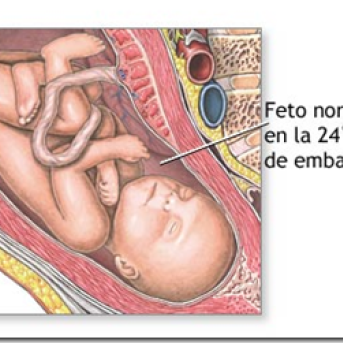

24 semanas

Já na 24ª semana, o crescimento do feto é muito rápido, chegando a pesar 500 gramas. O espaço na barriga fica cada vez mais apertado e seus movimentos cada vez mais bruscos, causando às vezes até sensações dolorosas na mãe. Seus pulmões estão cada vez mais maduros e preparados para iniciar a respiração assim que nascer. Muitas mães ficam sem saber com 24 semanas de quantos meses está, portanto falta pouco para completar o 6º mês

25 semanas